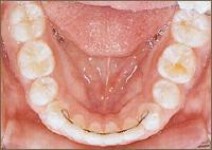

Die erste Zahnspange

Falls notwendig, werden neue Abdrücke genommen, um ein Gerät anfertigen zu können, oder es wird schon ein neues Gerät eingesetzt.

Ab jetzt spricht man von einer laufenden Behandlung. Alle 4-6 Wochen (je nach Gerät und Entwicklungsstadium) finden Kontrolltermine in der Praxis statt, um die Wirkung der Geräte zu überprüfen.